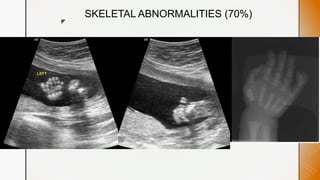

SKELETAL ABNORMALITIES (70%)